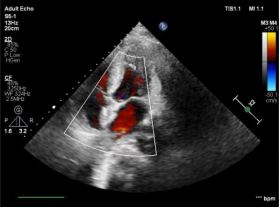

心血管内科主任医师程应樟诊断患者为先天性心脏病,卵圆孔未闭,反常栓塞导致脑梗死。为更好解决患者因封堵器植入产生心腔内异物心理负担,经患者要求,决定采用国际上最新的生物可降解封堵器治疗。据了解,该可降解封堵器可在 1 年内自然降解为水与二氧化碳,介导自体组织再生填充闭合卵圆孔,真正实现「介入无植入---无痕补心」之效果。

在程晓曙教授、吴清华教授、吴延庆教授及心血管内科全科医务人员支持下,程应樟教授团队联合超声张诗渊教授及心脏介入室护技人员为该患者制定了精准的治疗方案。在海军军医大学附属长海医院秦永文教授指导下,成功为患者进行了生物可降解卵圆孔未闭封堵器介入治疗。